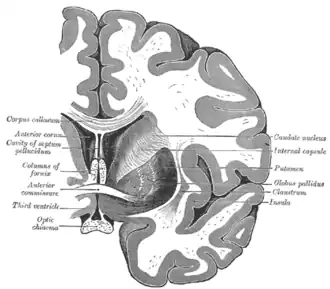

Coronal section through anterior cornua of lateral ventricles. -

Coronal section of brain through anterior commissure. -